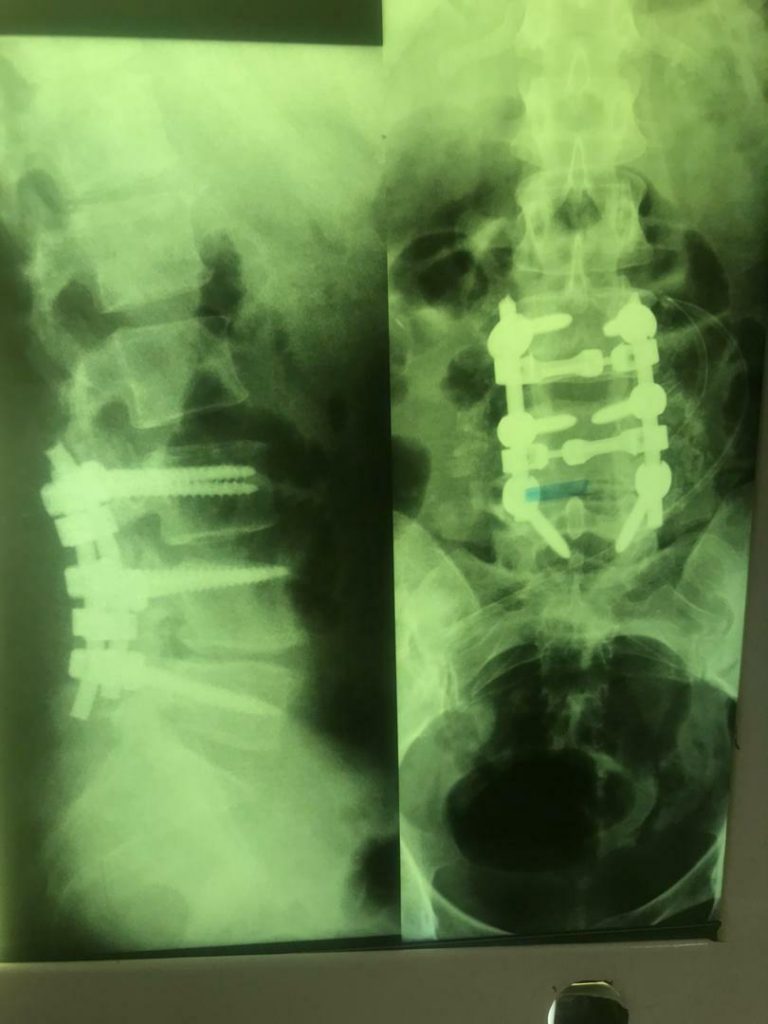

جراح ستون فقرات و دیسک کمری

4. بیماری‌های ستون فقرات

11. دیسک کمر و گردن